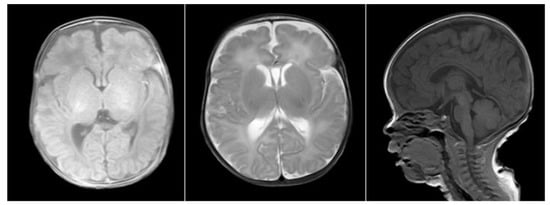

2. Case Report

2.1. Clinical Data